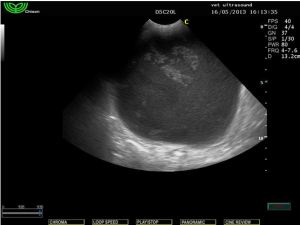

Ευρήματα: Στον υπέρηχο εντοπίστηκε μικρή παρουσία ασκητικού υγρού και μία μάζα στρογγυλή σαφώς περιγεγραμμένη χωρίς να δείχνει να έχει πρόσφυση σε κάποιο όργανο. Το τοίχωμά της φαινόταν αρκετά παχύ και στο εσωτερικό υπήρχε παρουσία παχύρρευστου υγρού. Στη διαφορική διάγνωση υπήρχε η υποψία για κάποιο απόστημα της περιτοναικής κοιλότητας, κύστη του μεσεντερίου και η δίλοβος εντερική κύστη (intestinal duplicated cyst). Μετά από χειρουργική εξαίρεση βρέθηκε πως η κύστη αυτή ήταν κολλημένη πάνω στο παχύ έντερο από την μία πλευρά και από το μεσεντέριο από την άλλη. Το περιεχόμενο ήταν μία άμορφη ουσία παχύρρευστη. Το τοίχωμα της κύστης έμοιαζε με το τοίχωμα του εντέρου. Η διάγνωση τέθηκε τελικά ως δίλοβος εντερική κύστη.